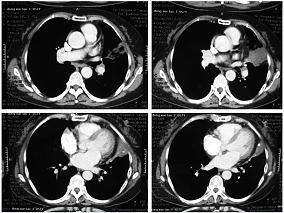

1小时条评论患者男性,75岁,于2008年4月15日入院。 一、主诉 急性阑尾炎术后第二天,突发呼吸困难2小时。 二、病史询问 (一)初步诊断思路及问诊目的 患者为老年男性,急性阑尾炎术后,急性起病,以呼吸困难为突出的临床表现而请求会诊。首先想到的是患者的呼吸困难是心...